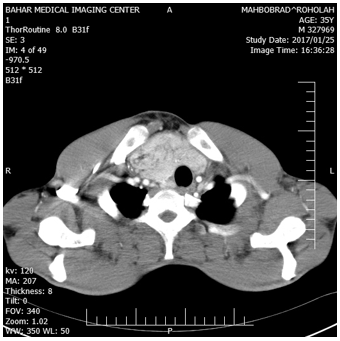

Figure 4: CT scan of neck showing a mass to occupying total thoracic inlet with strands and islands of soft fatty tissue.

Haematological and serological investigations, including tumor markers (alphafetoprotein, lactate dehydrogenase, beta human chorionic gonadotrophin, and alkaline phosphatase) were normal and not contributory to the diagnosis. With these radiologist report, the patient underwent to US-needle biopsy identified atypical cell and suspicious to liposarcoma. On completion of the preoperative evaluation, a right extensive posterolateral thoracotomy was performed via the fifth intercostal space. a large, encapsulated, vaguely lobulated mass was found within the anterior mediastinum. The mass arose in the anterior mediastinal fat, increasing in size as it extended above to the right side of neck and to the superior vena cava to the right inferior pulmonary vein, and extended to left hemithorax, compress the heart, diaphragm and shifted the mediastinum to the left, The mass occupied approximately 90% of right and 30% of left pleural cavity, resulted in marked compression and totally collapsed of right lung and partially collapse of left upper lobe (Figure1-4).